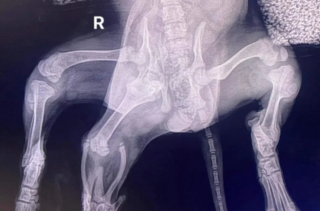

La chienne présente en fait des membres en trop. Après des examens, le vétérinaire de la clinique Medivet, située à Pembroke, dans le sud-ouest du Pays de Galles, a constaté qu’elle avait 6 pattes.

En plus de cela, les radios ont permis de déceler qu’elle avait aussi 2 organes génitaux.

La vétérinaire a donc confirmé qu’Ariel « a 2 pattes arrière supplémentaires et le début d'une seconde vulve. Son bassin ne s’est pas formé correctement à cause d’une articulation supplémentaire de la hanche ».

En pratiquant des examens plus poussés, Charlotte a mis en évidence qu’elle « n'a qu'un seul rein, deux utérus et divers autres doubles de vaisseaux sanguins... » Cela étant, Ariel a un comportement normal et ses organes fonctionnent bien heureusement de manière normale. « Elle aura probablement besoin de plusieurs interventions chirurgicales », explique encore Charlotte.